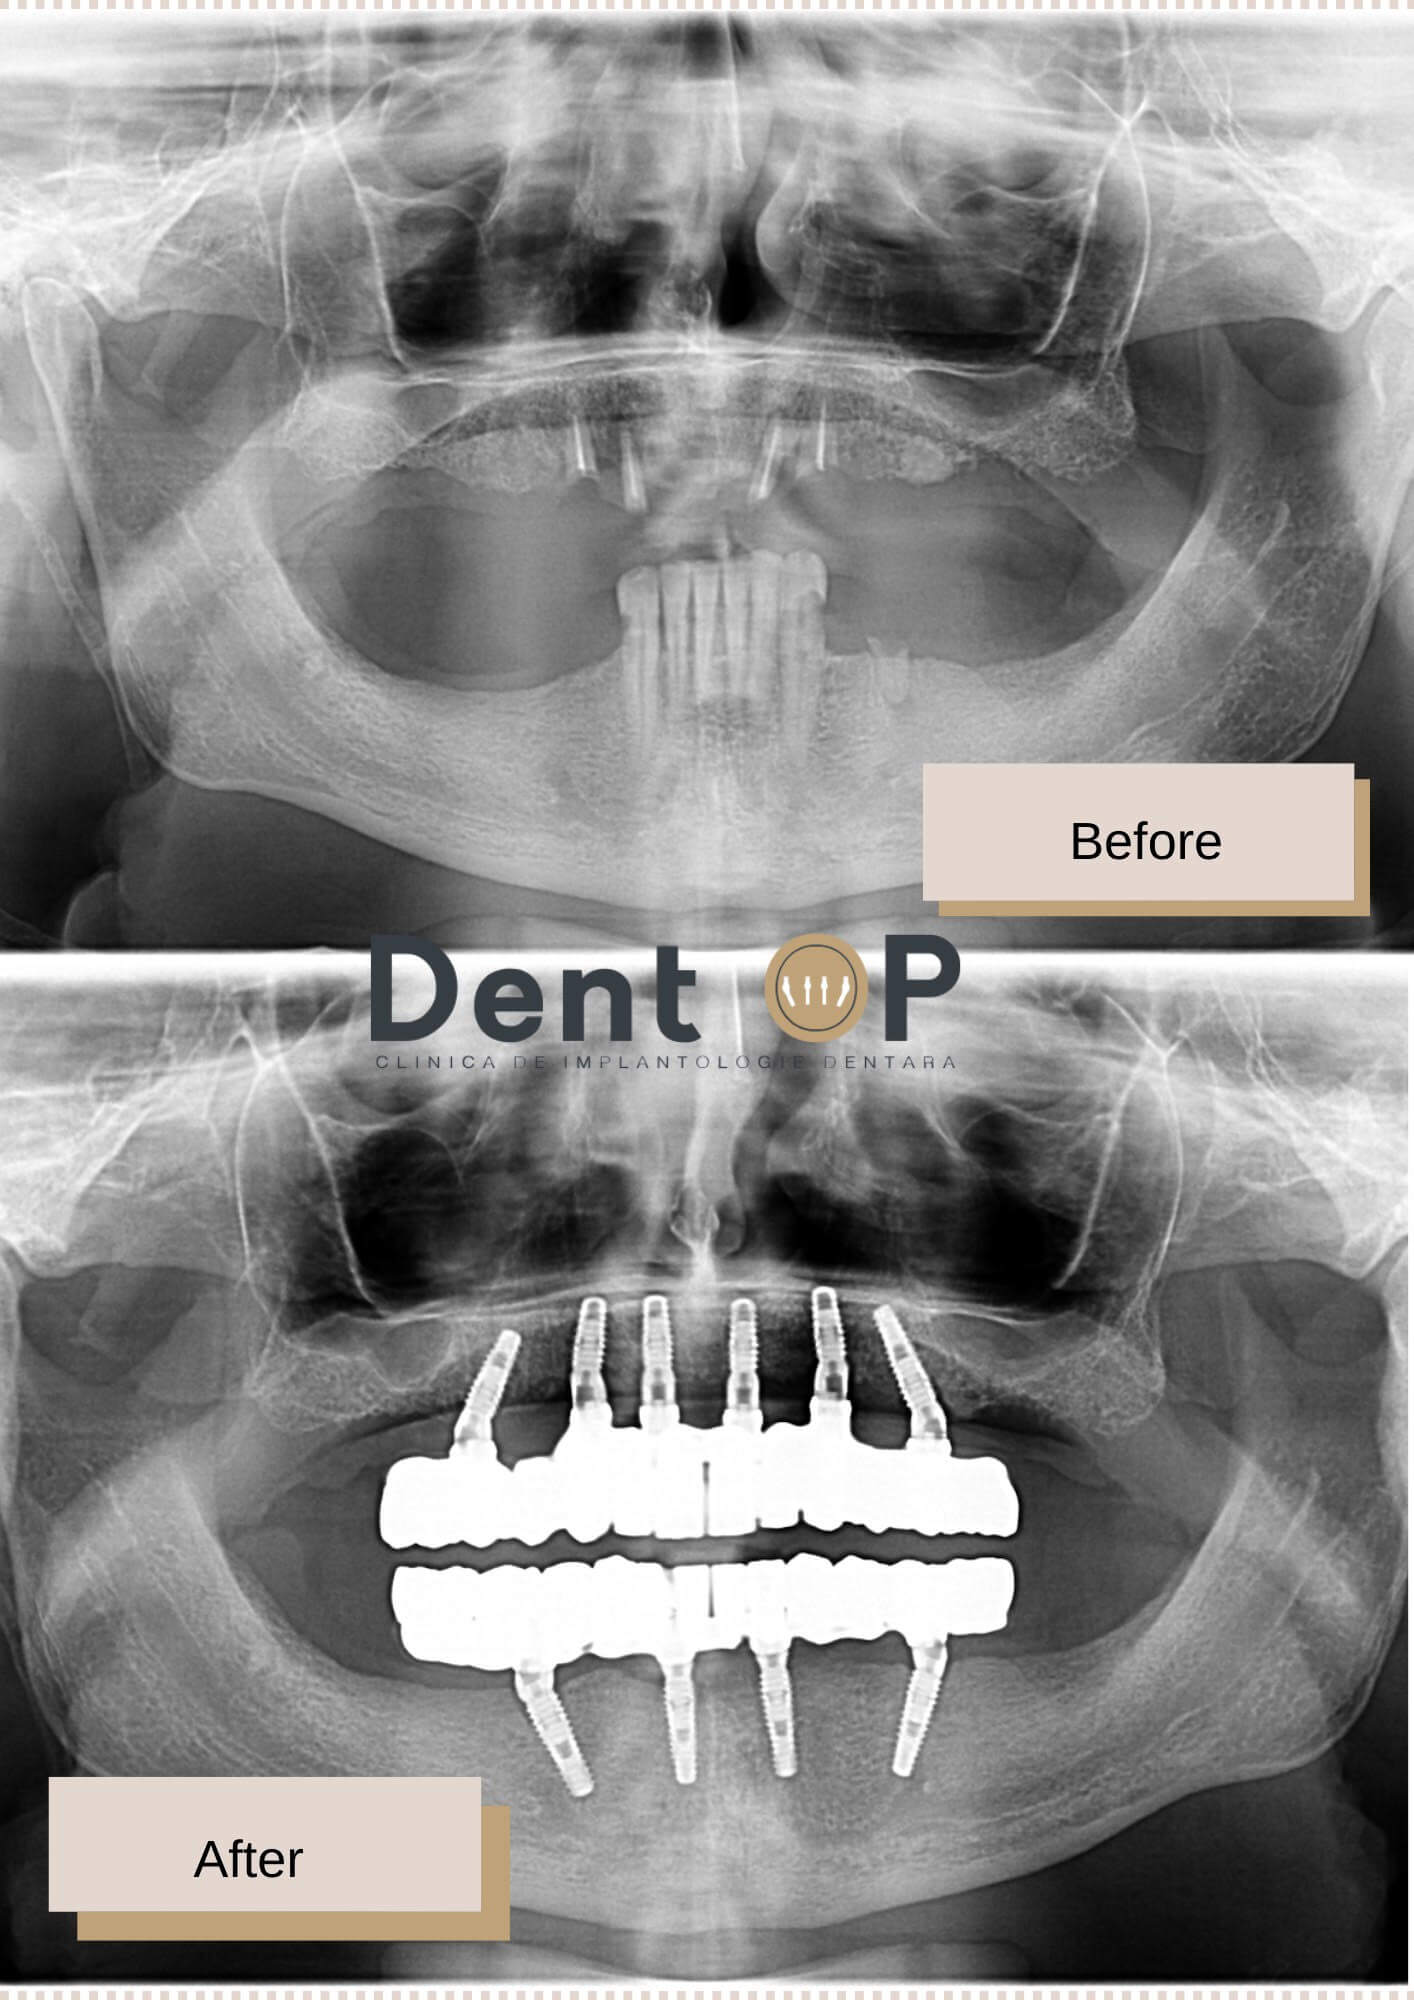

În cadrul consultației s-a realizat o radiografie dentară în cadrul clinicii pentru a vedea cât mai bine starea danturii sale. S-au observat 4 tratamente de canal efectuate la maxilar, dar care mai erau doar rădăcini deoarece nu a fost fixată o coroniță după tratament. La mandibulă au fost observate niște lucrări vechi care nu mai serveau pacientului la masticație.

Dr Cazacu Corrado- Medic Specialist Chirurgie Dento-Alveolară i-a propus un plan de tratament de reabilitare totală cu ajutorul a 10 implanturi dentare, 6 la maxilar și 4 la mandibulă. După 24h, pacientul s-a prezentat și pentru inserarea lucrărilor provizorii pe care le-a purtat timp de 6 luni.